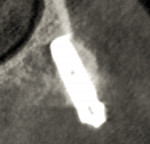

3D dentistry is truly transformative. By integrating computer-assisted implantology via GALILEOS® CBCT imaging (Dentsply Sirona Imaging, dentsplysirona.com) clinicians can confidently offer streamlined solutions for complex dental problems and provide advanced treatment options. Dentsply Sirona’s innovative SmartFix® concept affords implant dentists unique, reliable rehabilitation possibilities. The Astra Tech EV drilling protocol ensures primary stability for implant placement when immediately loading. Use of a digital workflow to diagnose and treatment plan removes guesswork, provides predictability, and ensures precision to return esthetics and function. The Profile EV implant, designed to follow the geometry of the alveolar ridge, decreases the need for bone reduction when tilting posterior fixtures by placing them at or slightly below the crestal bone. Restorative product options provide expanded choices with regard to angulations, tissue depths, and interocclusal spaces. Available prosthetic products simplify the restorative process for converting an immediate denture to an implant-retained fixed provisional prosthesis during the “teeth in a day” treatment procedure. As shown in this case, the patient gains expeditious improvement in esthetics, speech, and function with a single-staged, immediate-load, fixed hybrid prosthetic solution.

The Profile EV implant is designed to minimize marginal bone remodeling and improve crestal bone preservation, lessening the need for bone augmentation or reduction and enhancing postoperative healing.

Combining the Profile EV implant with planning software and using surgical guide safeguards enables precise placements with improved control of depth, angulation, and timing. The SmartFix concept streamlines all-on-4 oral rehabilitation.